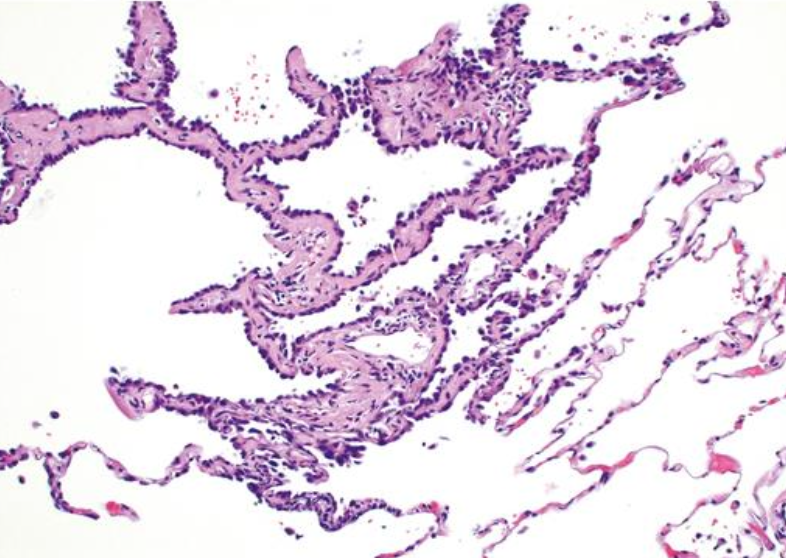

<p>Adenocarcinoma in situ</p>

Adenocarcinoma in situ

• Mide < 3cm

• Cél displásicas de alto grado a lo largo de los septos alveolares